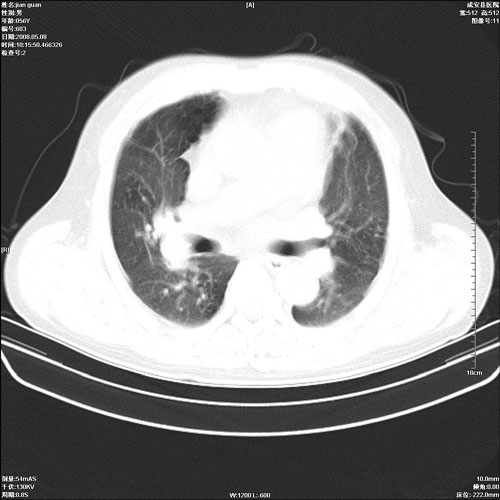

病人 男 60岁 主诉 胸闷 无明显发热 一般情况尚可。

两上肺陈旧性结核;慢支肺气肿、伴感染?

考虑1心功不全,肺水肿

2右上肺结核纤维性病灶、肺气肿

1.两上肺陈旧性结核;慢支肺气肿。

2.肺门血管扩张,心脏增大,为肺心病

考虑.两上肺陈旧性结核;慢支肺气肿。肺心病

1.陈旧肺结核;

2.慢支肺气肿;

3.肺心病.

2右上肺结核纤维性病灶、肺气肿 ,肺心病